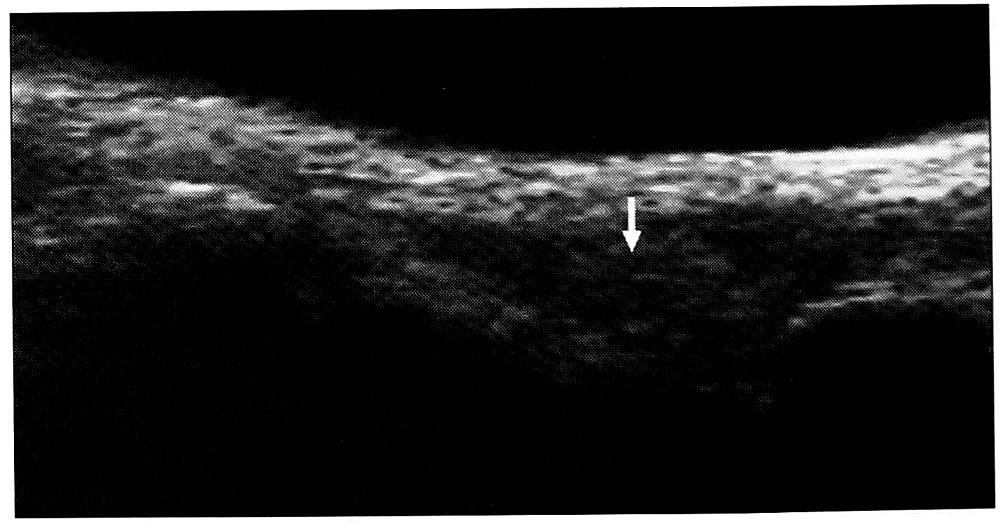

Период реабилитации. В раннем послеоперационном периоде за счет отека определялись увеличение диаметра сухожилия, сглаженность его контуров, неоднородность структуры. При плохой адаптации концов сухожилия обнаруживалась гипоэхогенная зона дефекта, контур его в некоторых случаях был деформирован. Через 10-14 дней в области сухожильного шва исчезала дифференцированная волокнистая структура, эхоплотность снижалась. При благоприятном течении послеоперационного периода диаметр сухожилия постепенно уменьшался, восстанавливалась его дифференцированная структура, контуры становились более четкими, эхоплотность повышалась (рис. 4). Динамические изменения в области сухожильного шва наблюдались на протяжении нескольких месяцев. Через 4~6 мес после восстановительной операции исчезала асимметрия геометрических характеристик.

Рис. 4. Продольная сонограмма сухожилия разгибателя III пальца на уровне головки пястной кости через 4 нед после операции. Удовлетворительная адаптация концов сухожилия, эхоплотность сухожилия в области шва снижена (стрелка).

Осложнения повреждений. Развитие спаечного процесса вызывало более глубокое нарушение дифференцированной волокнистой структуры сухожилия, повышение его эхоплотности. Контуры сухожилия становились нечеткими, в окружающих тканях появлялись дополнительные эхоструктуры (рис. 3, а и рис. 5). При динамическом исследовании отмечалось уменьшение подвижности сухожилия или ее отсутствие. В случае резко выраженного спаечного процесса сухожилие было неотличимо от окружающих мягких тканей — определялся единый высокоэхогенный конгломерат недифференцированной структуры. Границы распространения спаечного процесса выявляли путем исследования различных срезов. При тендините отмечались утолщение сухожилия, нарушение его дифференцированной волокнистой структуры, мозаичная эхогенность (см. рис. 3, а). Теносиновит характеризовался появлением в прилежащем к сухожилию участке зоны однородной структуры резко пониженной эхогенности с четкими краями, которая соответствовала расположенной в синовиальном влагалище полости, заполненной жидкостью (рис. 6). Дистрофические изменения сухожилия сопровождались уменьшением его диаметра, исчезновением дифференцированной волокнистой структуры и образованием аномальных областей повышенной эхогенности (см. рис. 6). При развитии паратенонита сухожилие было утолщено за счет паратенона, его эхографическая структура не изменялась.

Рис. 6. Продольная сонограмма сухожилий сгибателей III пальца на ладонной поверхности кисти. Определяется зона пониженной эхогенности неоднородной структуры — явления теносиновита (стрелка). Диаметр сухожилий уменьшен, дифференцированная волокнистая структура утрачена (симптомы, характерные для дистрофических изменений сухожилий)